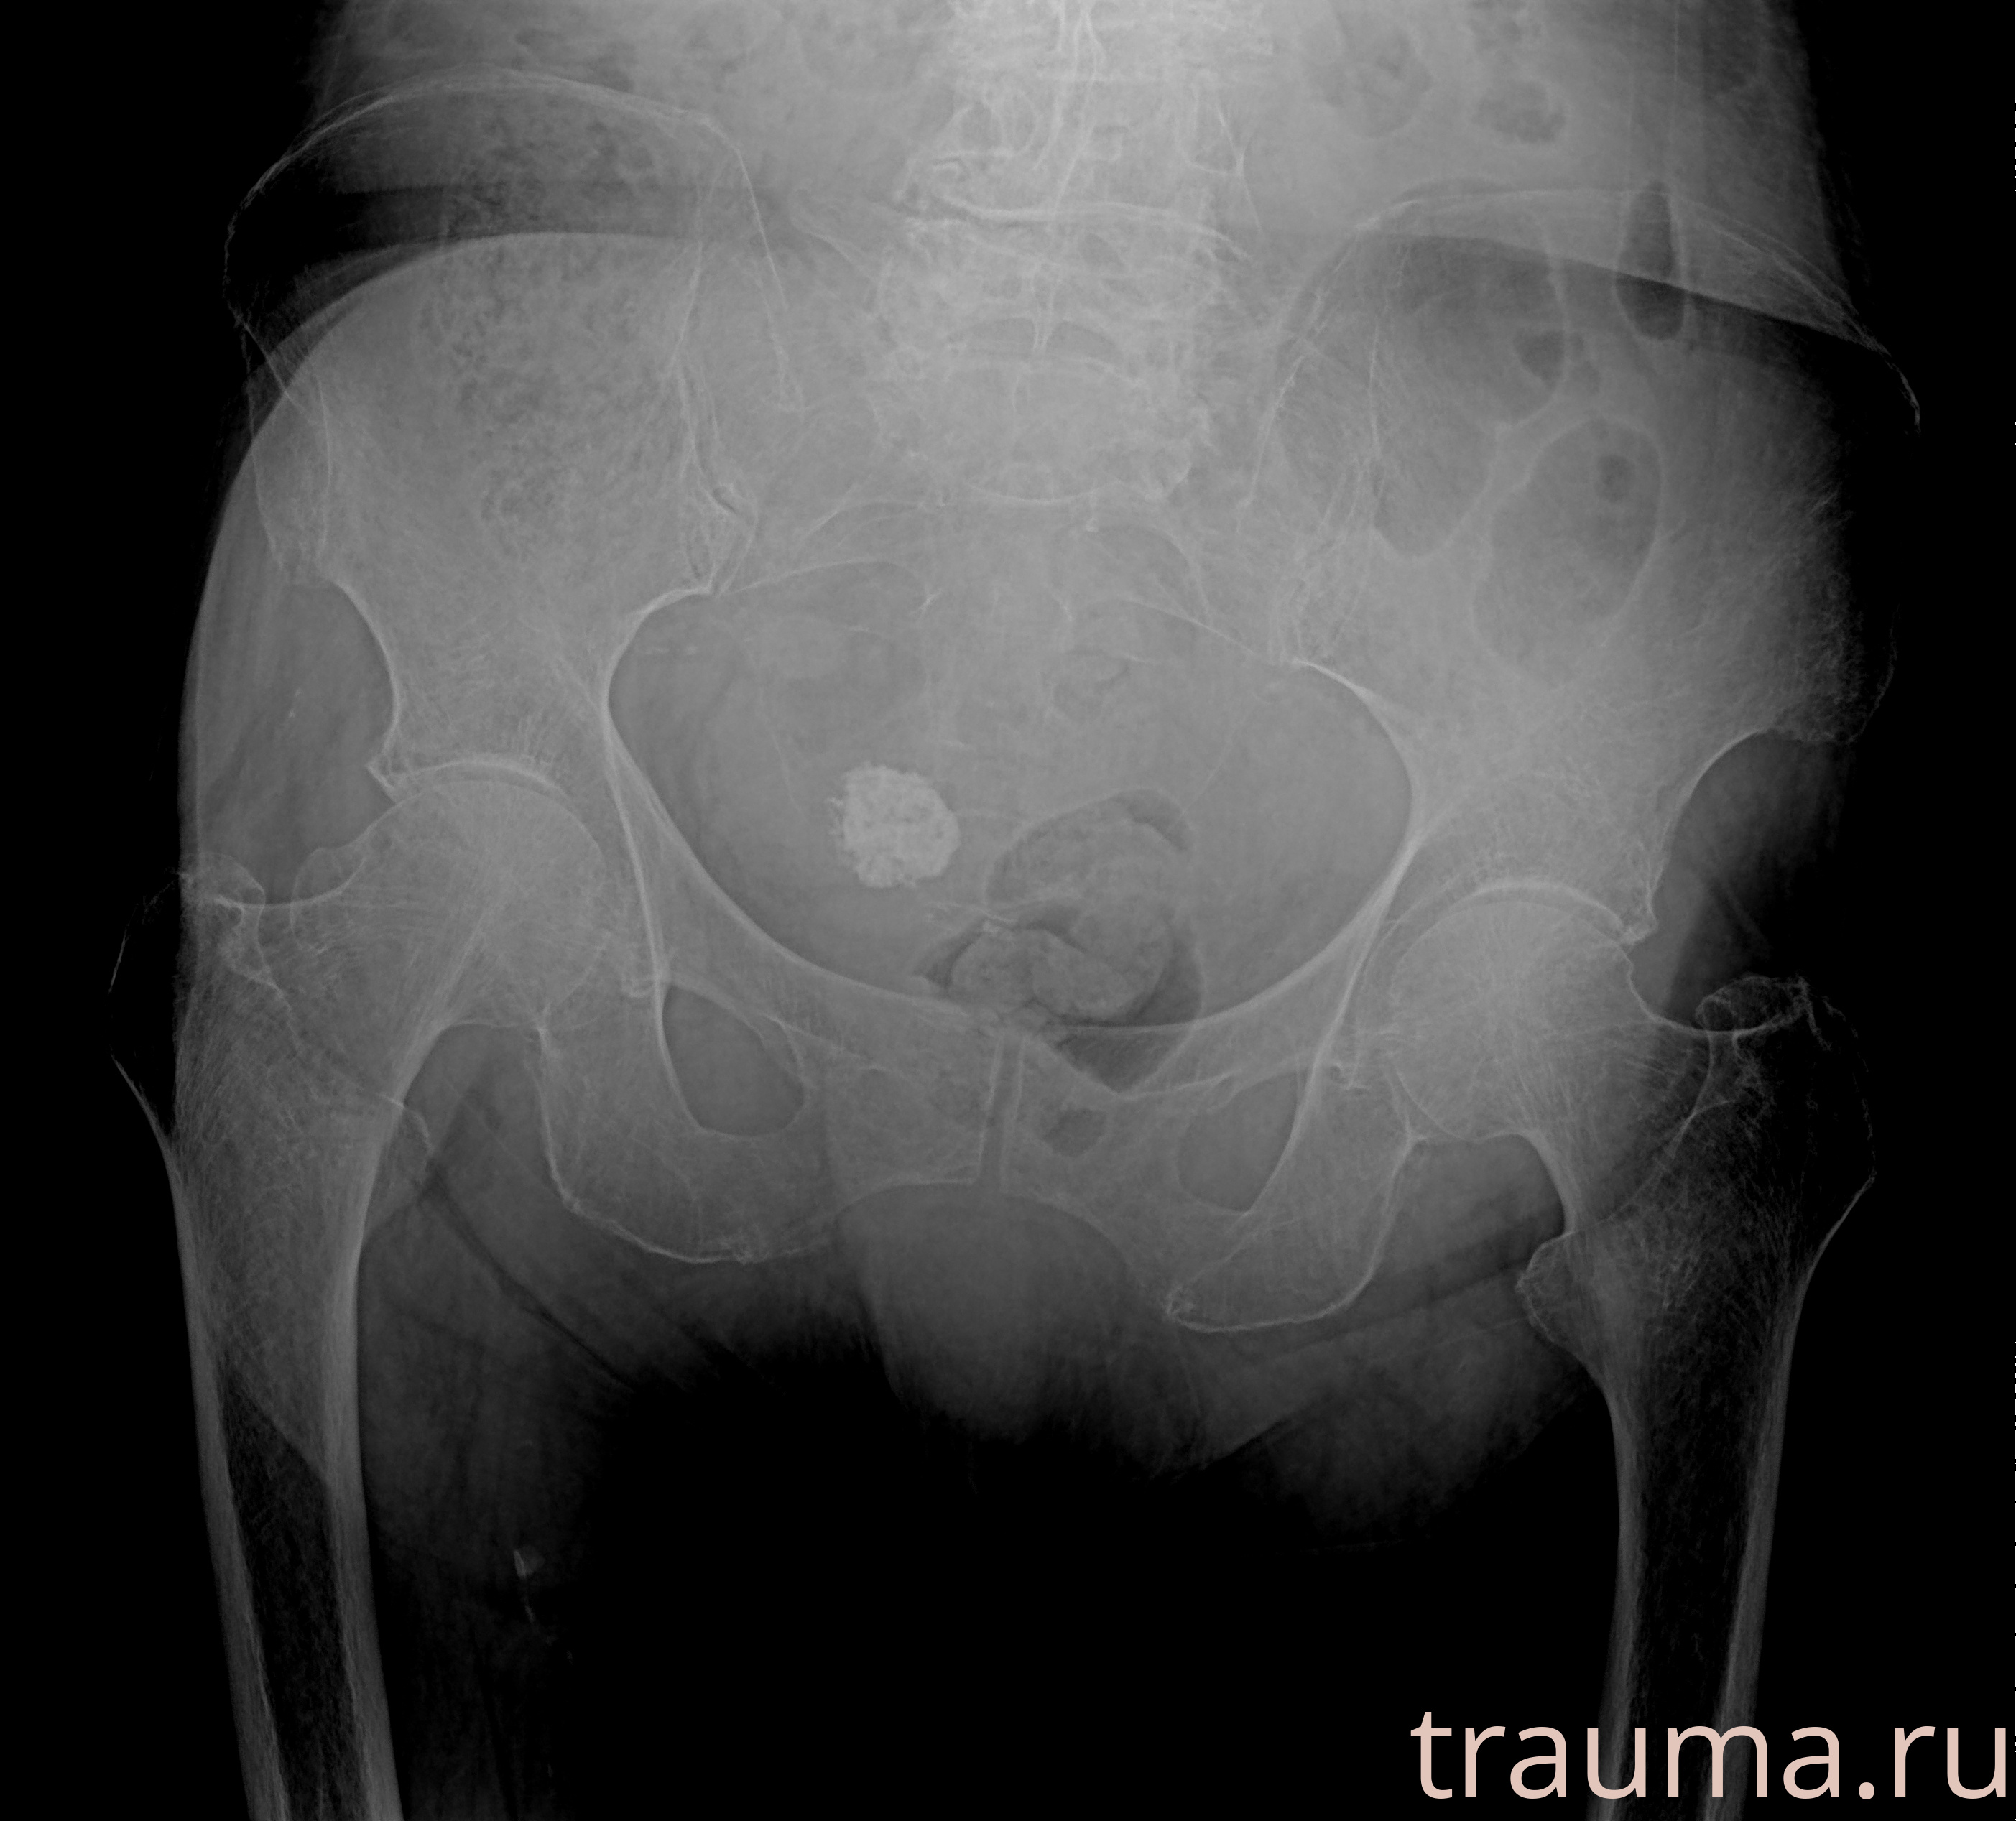

Рентгенограммы

Рентген на дому: по вашему адресу приезжает врач-рентгенолог, травматолог-ортопед с мобильным рентгеновским аппаратом, проводит диагностику травмы или заболевания, делает необходимые рентгенограммы, дает рекомендации по дальнейшему лечению. Получить качественные снимки в домашних условиях возможно благодаря уникальной методике, разработанной МосРентген Центром для института  Склифосовского